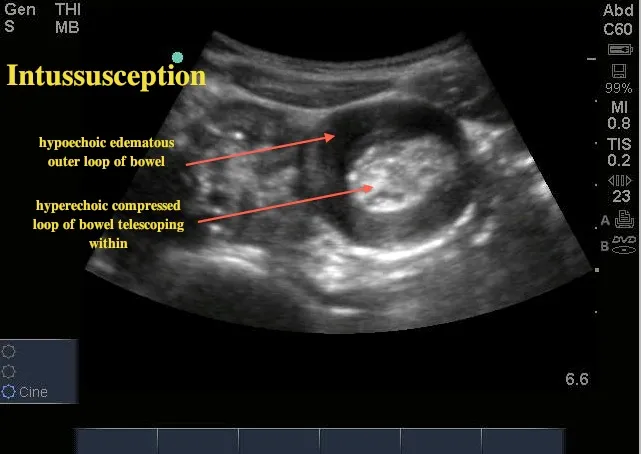

- Intussusception: Telescoping of the bowel, causing obstruction.

- Small ↑ risk with Rotavirus vaccines (RV1, RV5).

- Presents as colicky pain, vomiting, and red currant jelly stool.

⭐ The highest risk of intussusception after the rotavirus vaccine is within the first 7 days following the first dose.